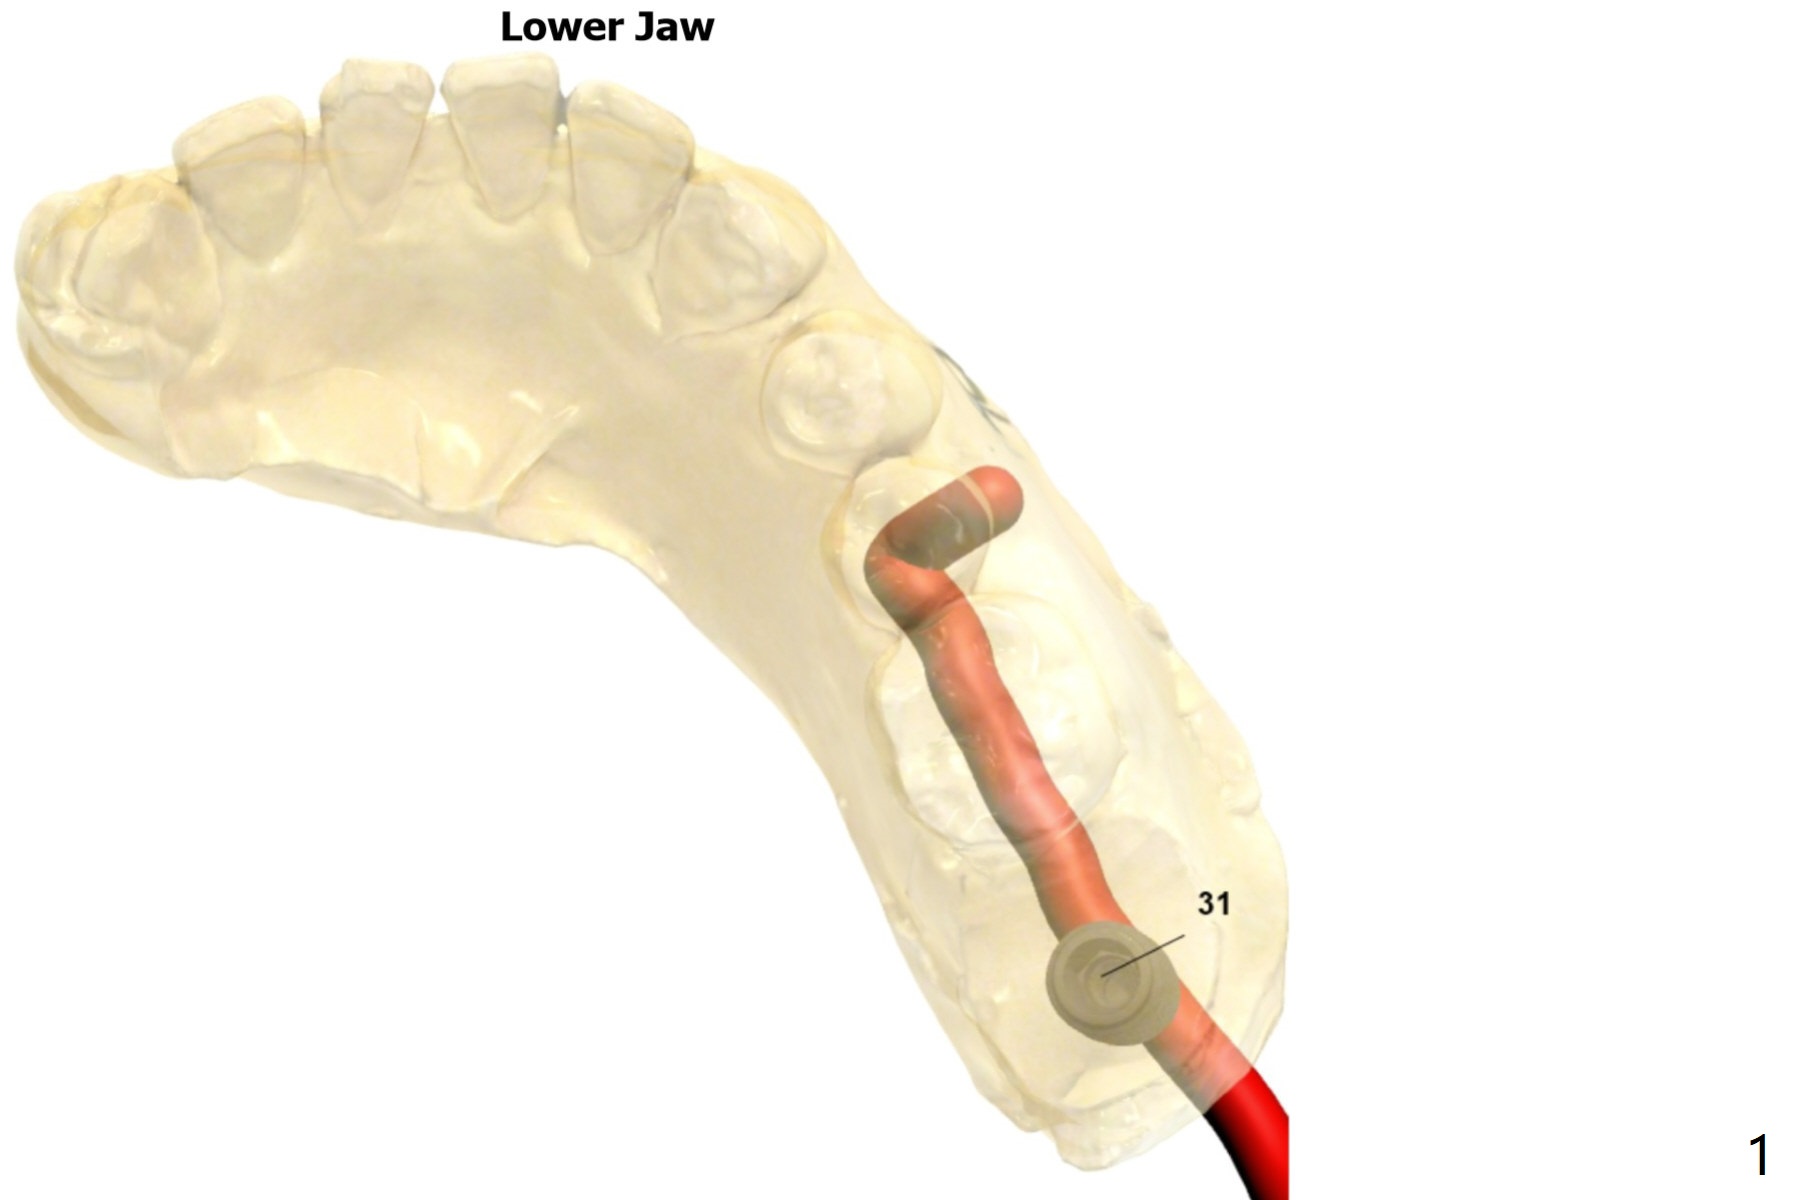

A 40-year-old man requests extraction of the tooth #31 with severe bone loss. PRF will be prepared for sticky bone and membranes (x2).

Lower

Molar Immediate Implant,

Prevent Molar Periimplantitis (Protocols,

Table),

Trajectory II,

No Antibiotic